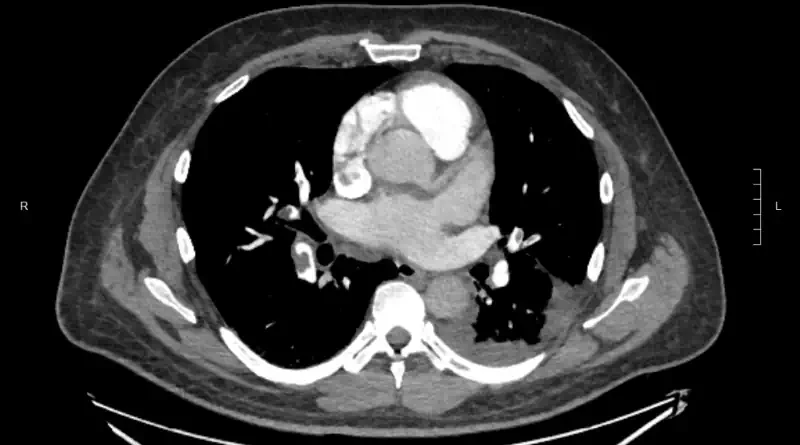

We diagnose clots in the lungs with imaging studies. The most common way to make the diagnosis is with a CT scan. Here is an example of a CT scan showing blood clots in the arteries of both lungs:

A CT scan involves radiation and contrast dye. So not every patient can have this test. Another test to diagnose pulmonary embolism is called ventilation / perfusion scan (V/Q scan).